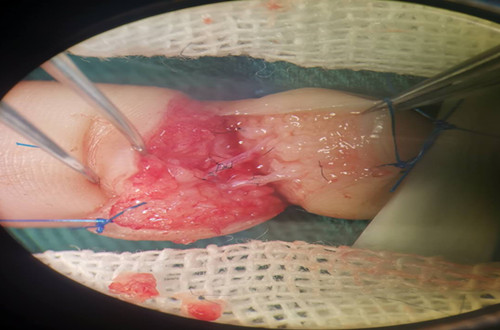

手術(shù)資料如圖示:

侯曉進主任帶領(lǐng)醫(yī)師岳賢峰、魏石磊歷時2小時,成功再植離斷指體。觀察指體張力適中,皮溫、皮色正常,毛細血管充盈實驗正常。術(shù)后予以對癥治療,按時傷口換藥,保持清潔。再植指體存活良好。于2019年1月22日間斷拆除傷口縫線后,患兒治愈出院。